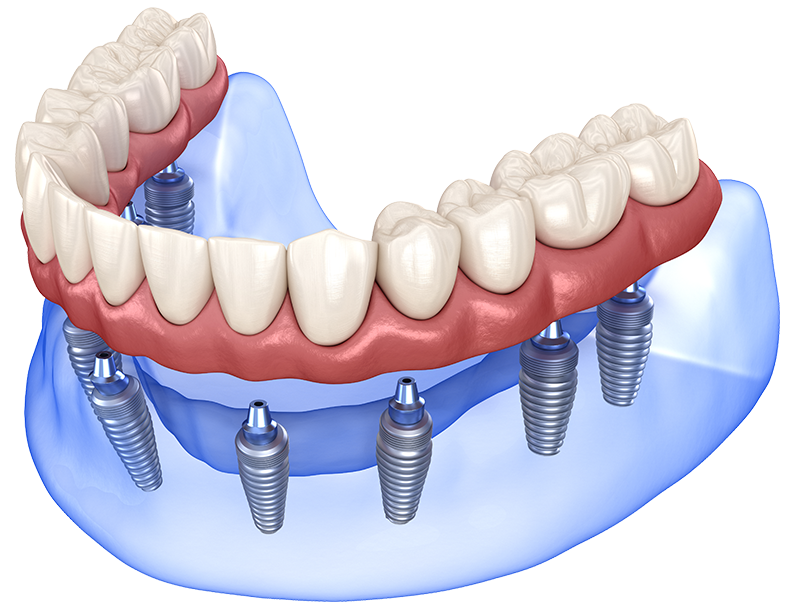

전체 임플란트

충치, 잇몸질환, 사고 등의 이유로

치아가 전부 상실된 경우

고정식으로 치아를 모두 재현하는 시술로 기능 회복 뿐만 아니라

전반적인 상황을 고려해야 하므로 경험이 많은 시술자에게 받아야 합니다.

• 고정

씹는 힘으로

임플란트가 움직이지 않게

고정

• 연결

식립한 임플란트와

보철물이 어긋나지 않게

정밀한 연결

• 분산

힘이 한 군데로

쏠리지 않도록 구조적으로

하중 분산

• 교합

주변 치아의 적절한 조화를

위해 힘의 균형을 맞추도록

조정